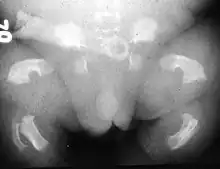

- La dysplasie épiphysaire multiple (ou polyépiphysaire) : Les points épiphysaires de croissance des os longs sont touchés, d'où une taille plus ou moins réduite.